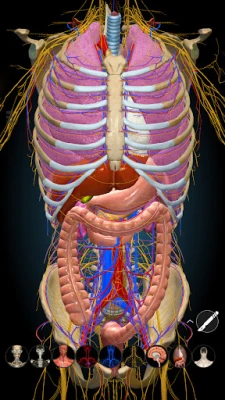

A true and totally 3D app for studying human anatomy, built on an advanced interactive 3D touch interface.

★ You can rotate models to any angles and zoom in and out

★ Remove structures to reveal the anatomical structures below them.

★ Switch on/off different anatomy systems

★ Circulation (arteries, vein and heart)

★ Central nervous system

★ Peripheral nervous system

★ Respiratory

★ Digestive

★ Urinary